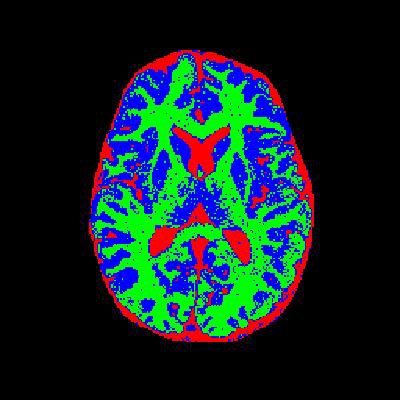

4. 实验结果与分析

通过实验验证,改进后的算法在噪声较多的图像上表现出了更好的鲁棒性和分割效果。以下是部分实验结果:

- 分割结果:如图3所示,改进后的算法能够有效地对目标区域进行分割,同时抑制噪声的干扰。